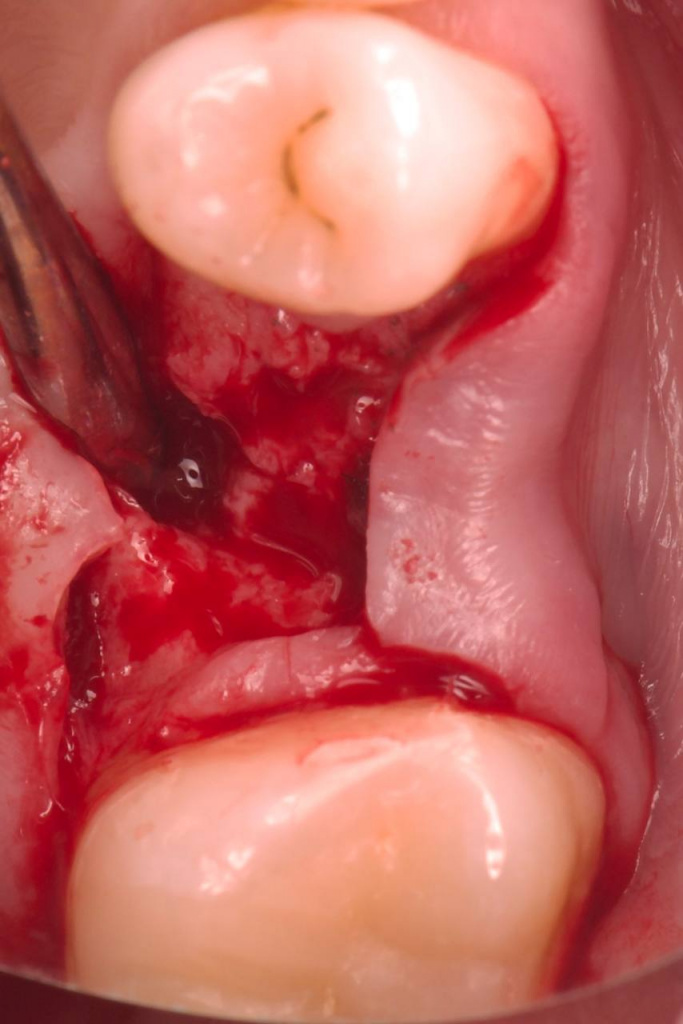

Открытый синус-лифтинг на губке и винте

Описание клинического случая:

• Открытый синус-лифтинг на губке и винте. Фиксация прямых мультиюнитов с усилием 30 Н/см

• После синус-лифтинга до установки имплантата прошло 3,5 месяца

Клинический случай Семерикова Дмитрия Юрьевича